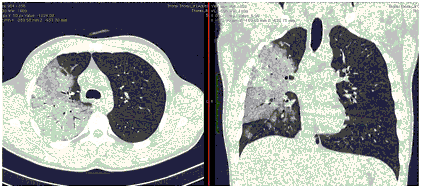

2. Наличие клинических проявлений, указанных в п. 1, в сочетании с характерными изменениями в легких по данным компьютерной томографии (КТ) (см. Приложение 1 настоящих рекомендаций) вне зависимости от результатов однократного лабораторного исследования на наличие РНК SARS-CoV-2 и эпидемиологического анамнеза.

- Изменения при КТ (рентгенографии), типичные для вирусного поражения (объем поражения минимальный или средний; КТ 1-2)

- Изменения в легких при КТ (рентгенографии), типичные для вирусного поражения (объем поражения значительный или субтотальный; КТ 3-4)

- Изменения в легких при КТ (рентгенографии), типичные для вирусного поражения критической степени (объем поражения значительный или субтотальный; КТ 4) или картина ОРДС.

КТ имеет высокую чувствительность в выявлении изменений в легких, характерных для COVID-19. Применение КТ целесообразно для первичной оценки состояния ОГК у пациентов с тяжелыми прогрессирующими формами заболевания, а также для дифференциальной диагностики выявленных изменений и оценки динамики процесса. КТ позволяет выявить характерные изменения в легких у пациентов с COVID-19 еще до появления положительных лабораторных тестов на инфекцию с помощью МАНК. В то же время, КТ выявляет изменения легких у значительного числа пациентов с бессимптомной и легкой формами заболевания, которым не требуется госпитализация. Результаты КТ в этих случаях не влияют на тактику лечения и прогноз заболевания при наличии лабораторного подтверждения COVID-19. Поэтому массовое применение КТ для скрининга асимптомных и легких форм болезни не рекомендуется.